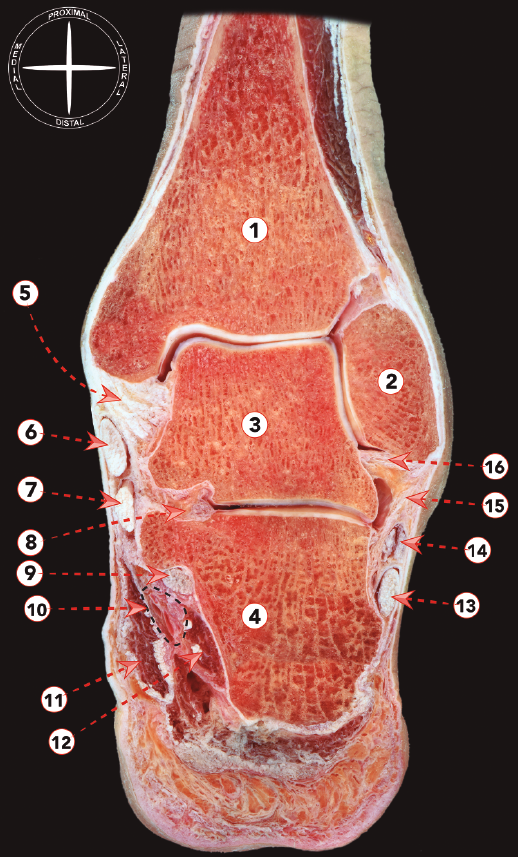

Este grupo de ligamentos que estabilizan las articulaciones tibiotalar y subtalar puede dividirse en complejo colateral lateral y complejo colateral medial (Figura 4).

Figura 4. Sección frontal de tobillo y articulación subtalar. 1: tibia; 2: maléolo fibular; 3: astrágalo; 4: calcáneo; 5: ligamento colateral medial; 6: tendón del tibial posterior; 7: tendón del flexor largo de los dedos; 8: ligamento talocalcáneo interóseo; 9: flexor largo del dedo gordo; 10: paquete neurovascular tibial posterior; 11: músculo abductor del dedo gordo; 12: músculo cuadrado plantar; 13: tendón del peroneo largo; 14: tendón del peroneo corto; 15: ligamento calcaneofibular; 16: ligamento talofibular posterior.